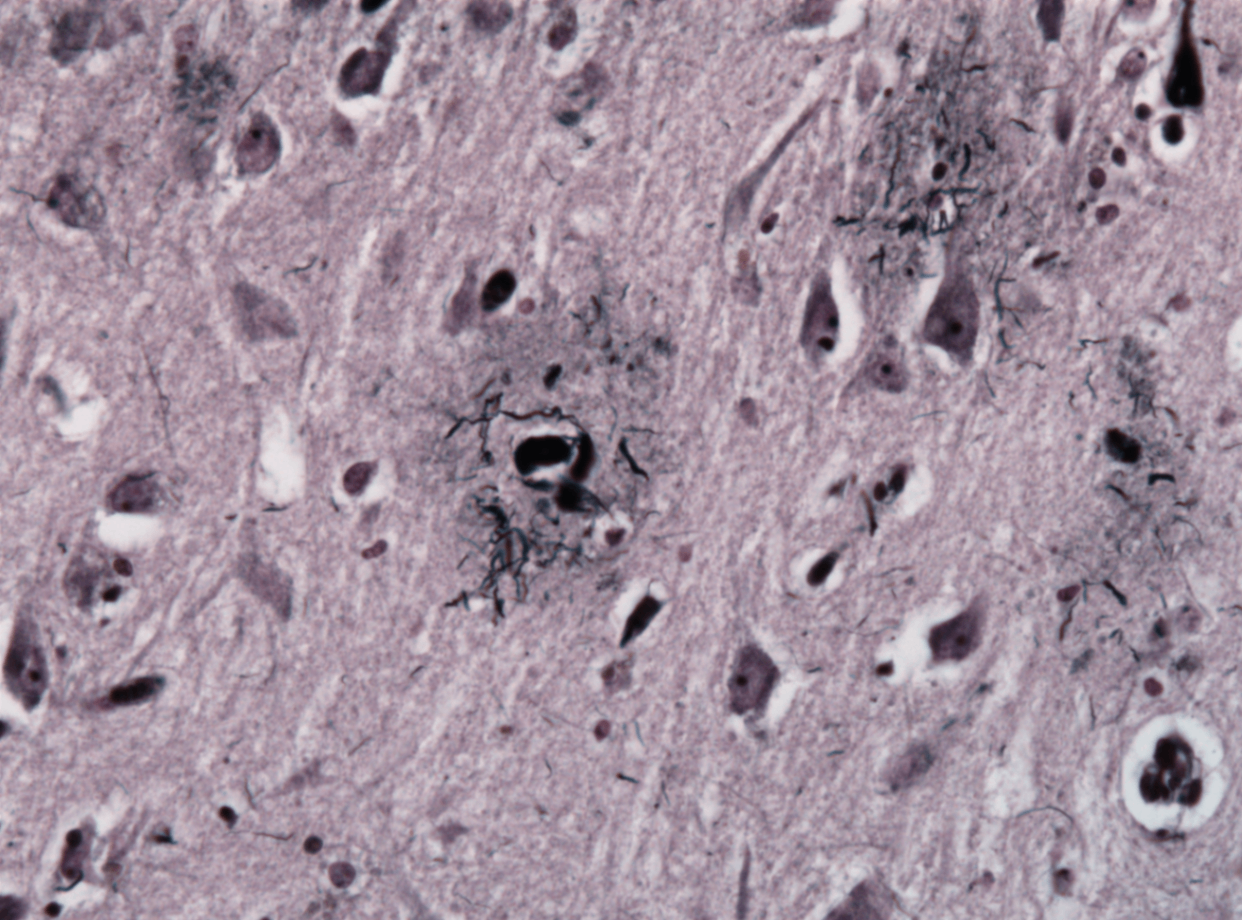

② Neurofibillary tangles

과인산화된 tau가 축삭 내에서 나선형 섬유 구조로 응집

• 고병기에서는 "flame-shaped" 모양

Histopathology of neurofibrillary tangles in Alzheimer's disease, Wikimedia CommonsAlzheimer neuritic plaque gallyas stain, Wikimedia Commons